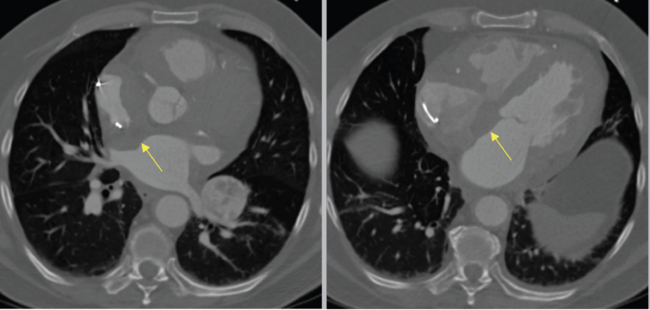

A 72-year-old male with past medical history of complete heart block status post pacemaker in 2019, renal cell carcinoma, and thyroid cancer presented with a 4-cm right atrial (RA) mass incidentally found on routine transthoracic echocardiography done to assess cardiac function after long-term immunotherapy. Cardiovascular computed tomography angiogram revealed an infiltrative mildly enhancing soft-tissue density along the right and left atrioventricular grooves, anterior interventricular groove, interatrial septum, free wall of the right ventricle, and RA (Figure 1).